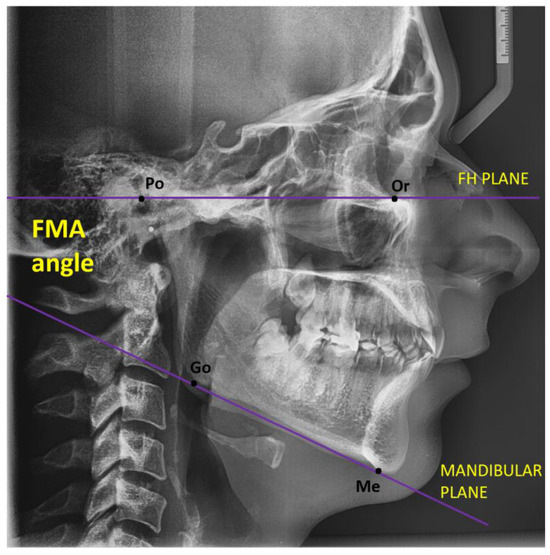

| FMA (degrees) | 22 (16, 26) |